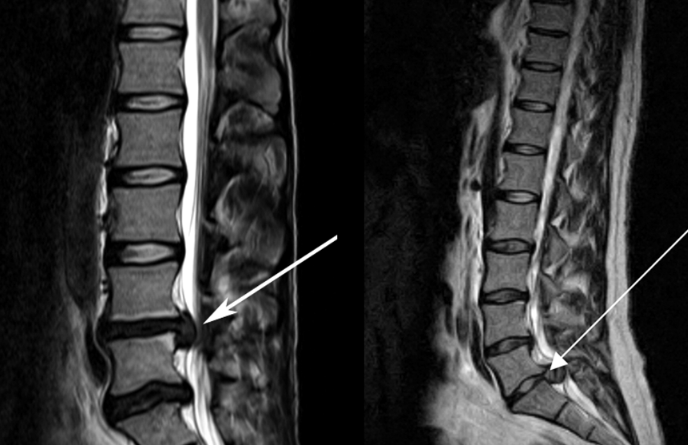

3、核磁共振(MRI):核磁共振沒有輻射,可以多方位成像(橫斷面、冠狀面、矢狀面和斜面),對解剖細節顯示較好,對組織結構的細微病理變化更敏感(如骨髓的浸潤),可以排除神經和脊柱腫瘤等。對于一些落到椎管的髓核組織也不會遺漏。